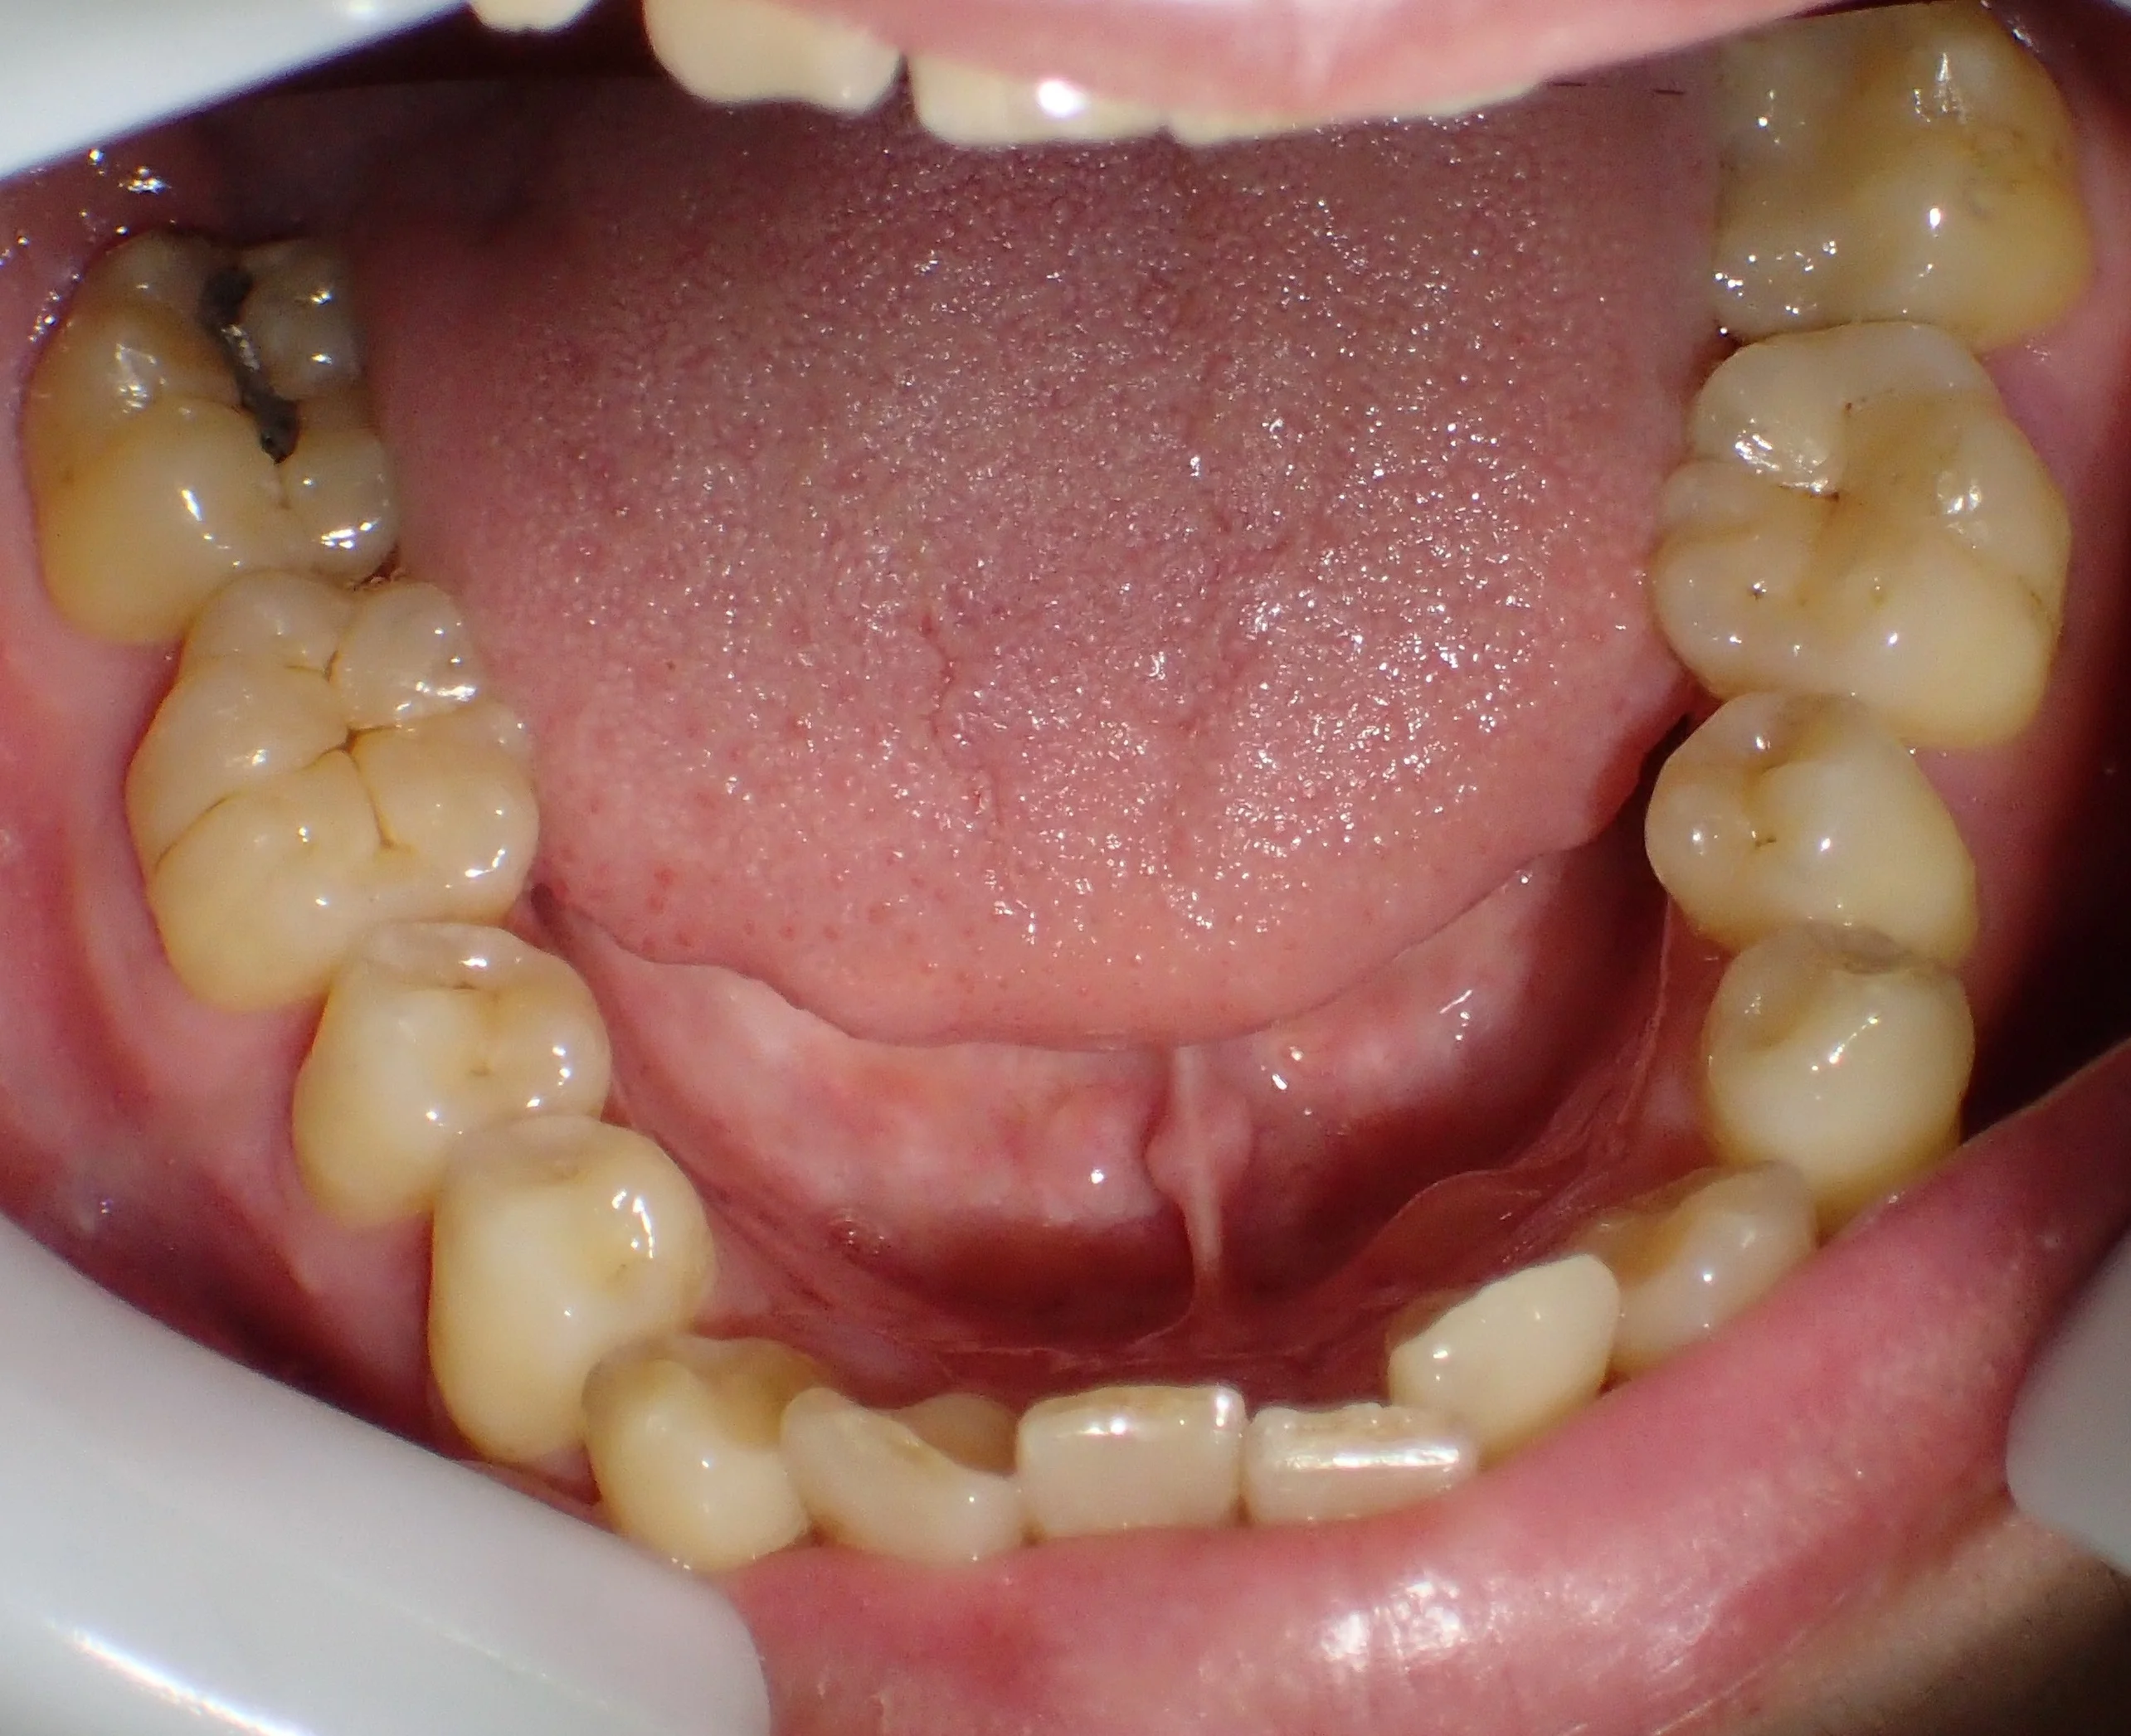

まだ坂寄歯科医院には全顎的にダイレクトボンディングで治療した症例がありませんので、前の医院にて治療を完了された方の写真を載せたいと思います。

どこを治療したかわかりますか?

答えは下の方に書いておきますので、スクロールしてください。

治療した箇所は、

・右上4,5,6

・左上4,5,6

・右下5,6

・左下5

でした!

治療した部位は全て元々詰めていたメタルインレーが再び虫歯になってしまった状態でした。

幸いあまり大きくは削られてはいなかったので、全てをダイレクトボンディングで治療することが出来ました。

右下7はアマルガムという金属が入っていますが、別にそこは虫歯にはっていなかったです。

なので、患者さんの同意の下、治療はせずにそのままにしています。